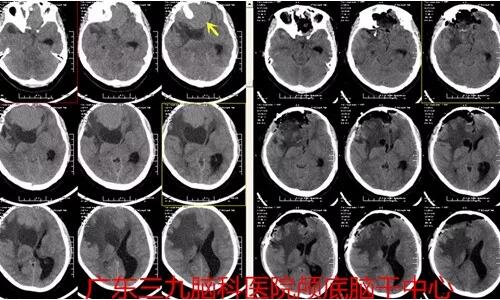

图3;术前术后对比肿瘤全切